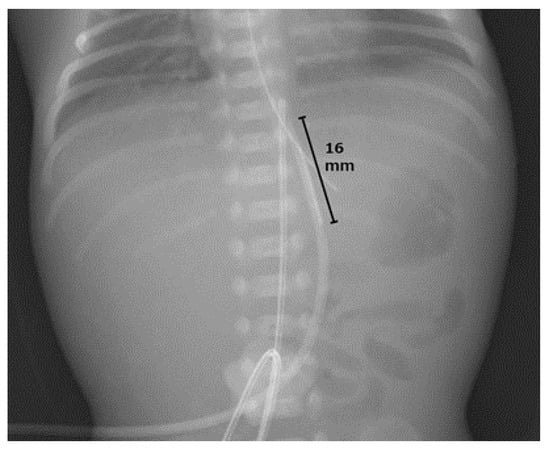

Umbilical Vein Calcification Associated with Double-Lumen Catheter Malpositioning in an Extremely Low-Birth-Weight Infant

2. Case Presentation